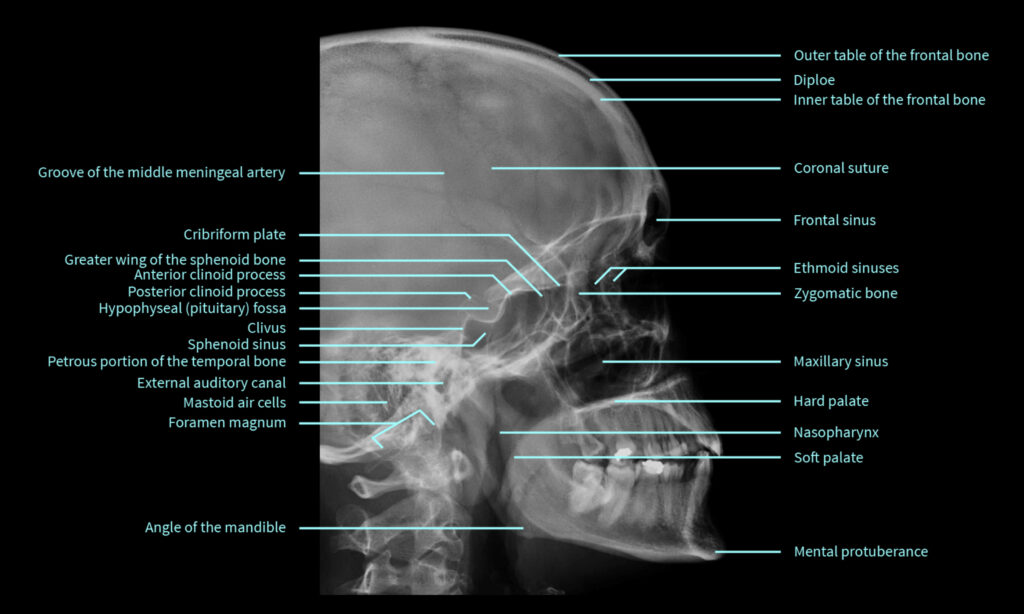

Từ hình ảnh chụp Xquang hay cộng hưởng từ MRI có thể xác định kích thước, hình dạng của khối u, từ đó có những cách điều trị phù hợp.